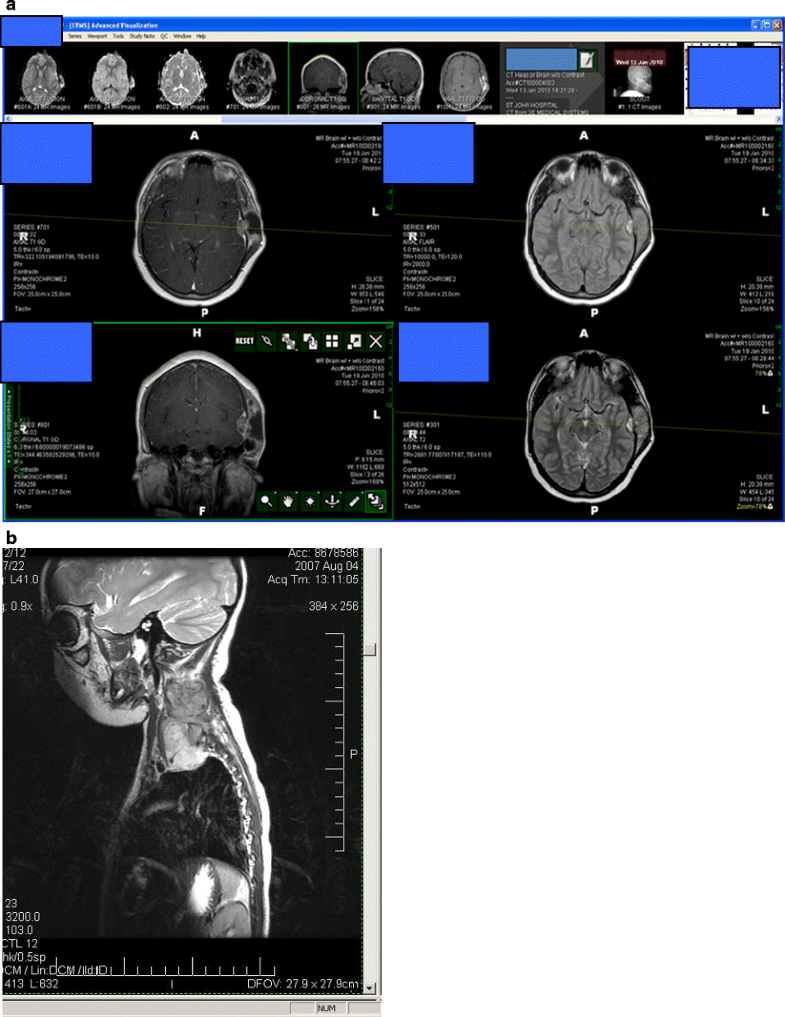

Unusual presentation of ewing s sarcoma 07 image This image demonstrates Unusual presentation of ewing s sarcoma 07.

- wide surgical excision: - preferred all over xrt if. Our case reports a same unusual case of ewing's sarcoma of spine. A multimodal access is often the treatment of prime in this rough neoplasm. Granulocytic sarcoma chloroma. Ewing's sarcoma, we practical rnai mediated composition profiling to describe kinase targets concerned in growth and survival of ewing's sarcoma cells. Ewing sarcoma can occur fashionable virtually any fix.